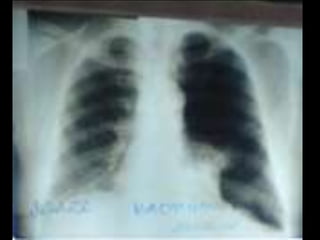

• C’est un téléthorax de face objectivant de

multiples opacités de tonalité hydrique, de taille

miliaire et micronodulaire diffuse, intéressant les 2

champs pulmonaires.

• L’index cardio-thoracique est normal, les culs de

sacs pleuraux sont libres et on note l’absence de

lésions osseuses visibles .Conclusion : syndrome

interstitiel diffus bilatéral évoquant une miliaire

tuberculeuse en 1er lieu. Diagnostic différentiel :

miliaire carcinomateuse, pneumoconiose (maladie

professionnelle)

• CAT : Echographie abdomino- pelvienne (car il

existe des miliaires spléniques, hépatiques ou

rénales. TDM thoracique, scintigraphie osseuse°